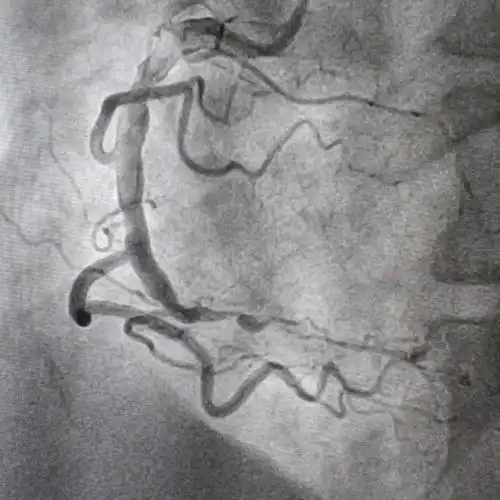

肌钙蛋白轻微升高,急诊冠脉造影显示右冠状动脉近段99%狭窄(图3)

这是一名心绞痛的患者,活动后明显胸痛,造影发现右冠状动脉明显狭窄